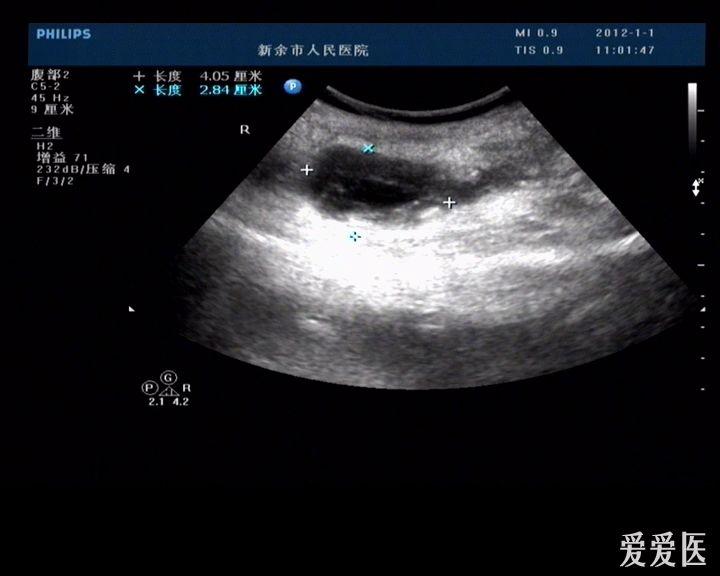

再发个典型的阑尾炎图像,请多提意见.

图片尺寸758x566